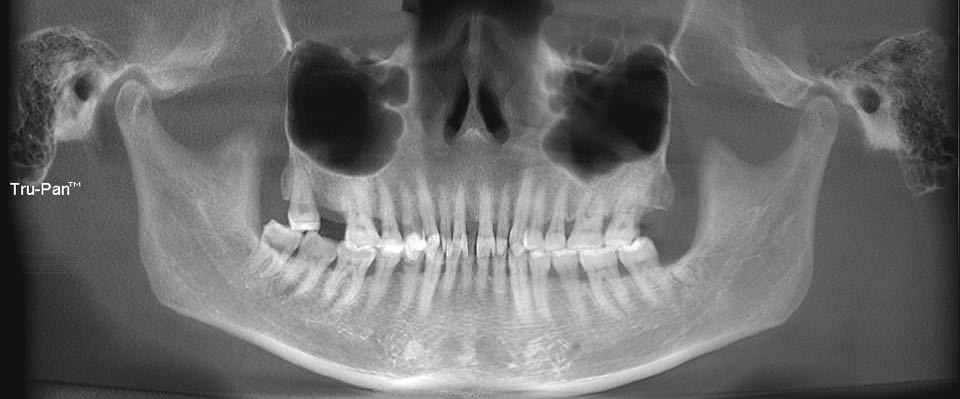

【术前全景片/CBCT】

术前全景片